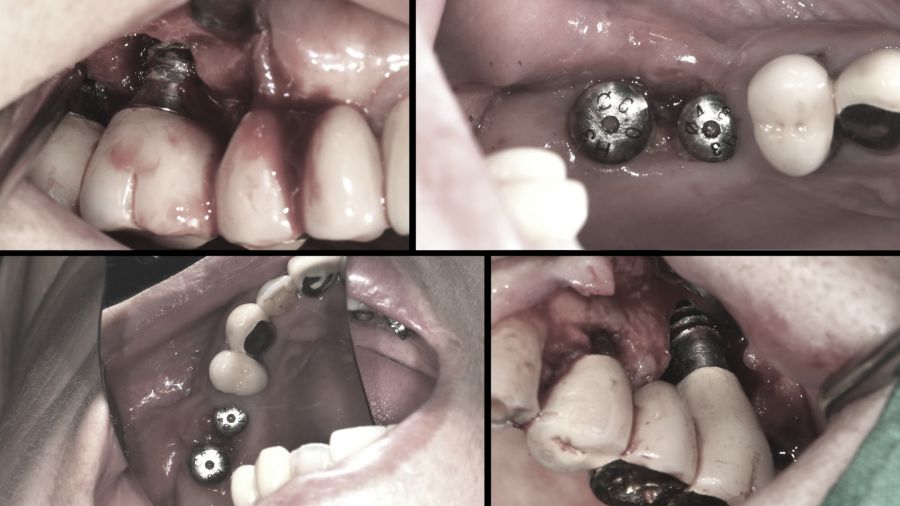

임플란트란 소실된 치아 자리에 티타늄 나사못을 심고 보철물을 얹어 치아 기능을 회복시키는 치료법이다. 임플란트는 금속 소재이기 때문에 충치가 생기지는 않는다고 알려졌지만 그렇다고 해서 문제가 없는 것은 아니다. 치주염이 생기듯 임플란트 주위 잇몸에 염증이 발생할 수 있기 때문이다. 임플란트 주위 잇몸에 염증이 발생하면 구취, 출혈을 유발하고 잇몸과 치조골의 손상을 불러오는데 이를 임플란트 주위염이라고 한다.

한 달 전부터 위쪽 어금니 임플란트에 통증을 느꼈다는 여성. 검사 결과 식립한 임플란트 고정체가 부러진 채 뼈에 박혀있는 상태였다. 실제로 통계에 따르면 임플란트 부작용 중에 나사 풀림과 파절이 약 49%로 1위를 차지한다.

임플란트의 나사가 풀리면 다시 조여주기만 하면 되지만 여성의 경우 나사가 잇몸에 고정된 채 부러져 제거하고 재식립 해야 하는 상황이다. 보철과 윤준호 교수는 임플란트를 제거하는 것은 임플란트를 식립하는 것보다 훨씬 어렵다고 말한다.

임플란트는 식립한 순간부터 주변 뼈와 유착이 이루어진다. 치주인대가 없이 나사못과 뼈가 바로 붙어 있기 때문에 제거 시 뼈 손상이 불가피하다. 따라서 신중하게 제거하지 않으면 상악동이 뚫리거나 하악의 경우 수많은 신경다발이 지나가기 때문에 신경 손상으로 마비, 통증 등을 유발할 수 있어 매우 신중해야 한다. 그렇다면 임플란트 제거술은 어떻게 진행되는 것일까? 임플란트 제거술과 나사 풀림과 파절이 발생하는 원인 및 임플란트를 망가트리는 습관 등을 자세히 알아본다.

3개월에 한 번 씩 정기검진을 받는다는 70대 남성. 하지만 불과 몇 년 전만 해도 치과를 자주 찾지 않았다는데… 그 결과는 끔찍했다. 식립한 임플란트 주위에 염증으로 잇몸이 녹아내린 것. 잇몸 일부를 잃고 나서야 관리의 소중함을 깨달았다는 남성. 실제로 많은 사람들이 임플란트를 식립하면 모두 끝이라고 생각한다.